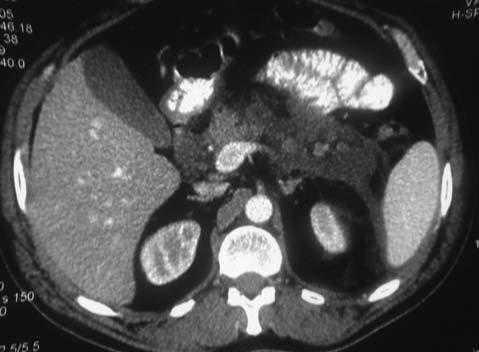

Fig.1.Pancreatitis aguda grave con importante desestructuración del tejido pancreático y líquido libre peripancreático y en celda renal como forma de inicio en un paciente afectado de hiperparatiroidismo primario por adenoma.

Varón de 30 años sin antecedentes de interés que refiere ingesta ocasional de alcohol sin tratamientos farmacológicos previos. Consulta en urgencias por un intenso dolor en epigastrio asociado a náuseas y vómitos. En la exploración resalta un intenso dolor a la palpación en epimesogastrio con defensa involuntaria y signos de irritación peritoneal. En la analítica se objetiva una leucocitosis de 22.400 con el 89% de neutrófilos, con amilasas en sangre y orina elevadas (1.850 y 3.420, respectivamente). La ecografía abdominal encontró una vesícula biliar normal sin litiasis con una desestructuración de la cabeza pancreática y líquido libre peripancreático. En la tomografía computarizada (TC) se halló una desestructuración completa de la glándula pancreática con líquido libre peripancreático (grado E de Balthazar) (fig. 1). Con el diagnóstico de pancreatitis aguda grave quedó ingresado en UCI; evolucionó favorablemente del cuadro abdominal, pero quedó como secuela una diabetes tratada con antidiabéticos orales. Un análisis de la serie iónica mostró: calcemia de 11,8 mg/dl, con fosforemia de 2,8 mg/dl. El análisis de paratirina (PTH) plasmática mostró unas concentraciones de 794 pg/ml, que así confirmó el cuadro de HPT primario. La ecografía cervical fue normal, y se observó hipercaptación de la glándula paratiroides inferior izquierda en el MIBI, compatible con adenoma, por lo que se indicó cirugía. El cribado genético del MEN I fue negativo. En la cirugía se objetivaron 3 glándulas normales, la inferior izquierda tenía aspecto adenomatoso y se extirpó. El análisis histológico confirmó el diagnóstico de adenoma de paratiroides. El paciente se encuentra asintomático 2 años después de la intervención, con cifras de calcemia normales y una TC abdominal de control que muestra un páncreas de morfología normal.